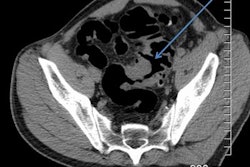

Several different classification systems of diverticular disease focus on measurements of colonic wall thickness and lumen dimensions, but many of these scoring systems are complicated and time-consuming. No gold standard exists.

Irish researchers have addressed this problem and proposed a simple, visual scoring system to classify the severity of diverticular disease. In developing this system, they've conducted an audit of more than 1,800 scans of the colon. Get the full details here.